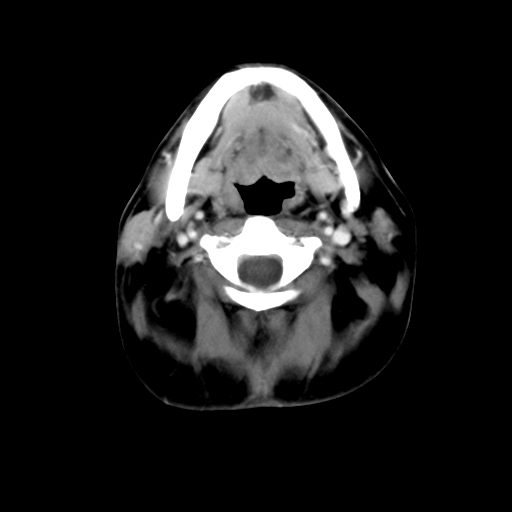

标题: CT24019:男,45岁,发现颈部肿物5个月。 [打印本页]

男,45岁,发现颈部肿物5个月,彩超示:双侧颈部及下颌部软组织增厚。

考虑双侧颈项部良性对称性脂肪增多症。